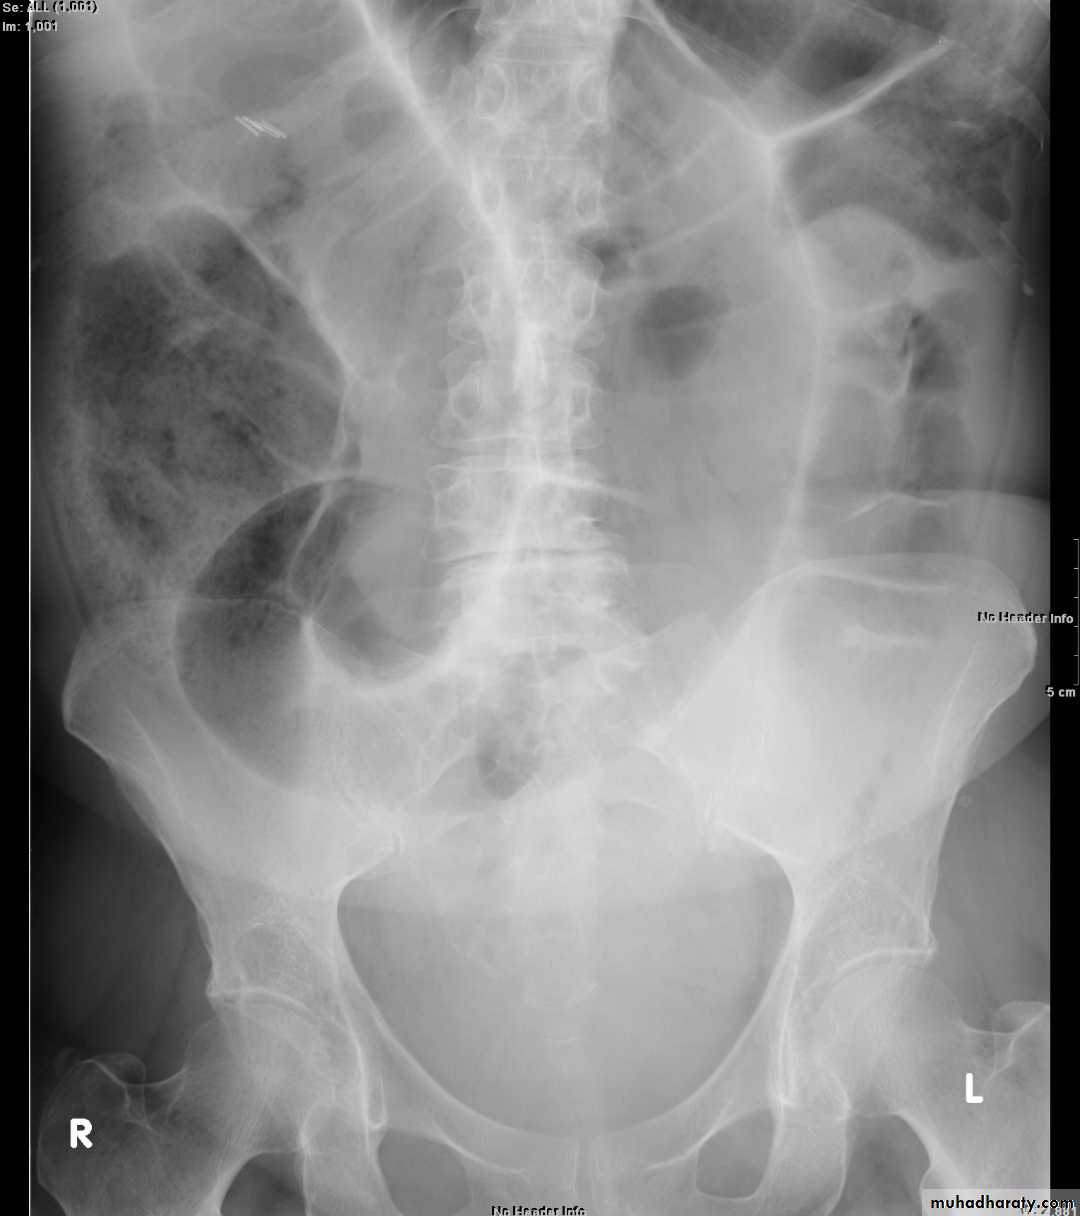

Large bowel obstruction (LBO) are often impressive on imaging, on account of the ability of the large bowel to massively distend. This condition requires prompt diagnosis and treatment

Radiographic features

Colonic distension > small bowel

Peripherally located

Dilated loops Less in no. than SBO

Presence of haustra